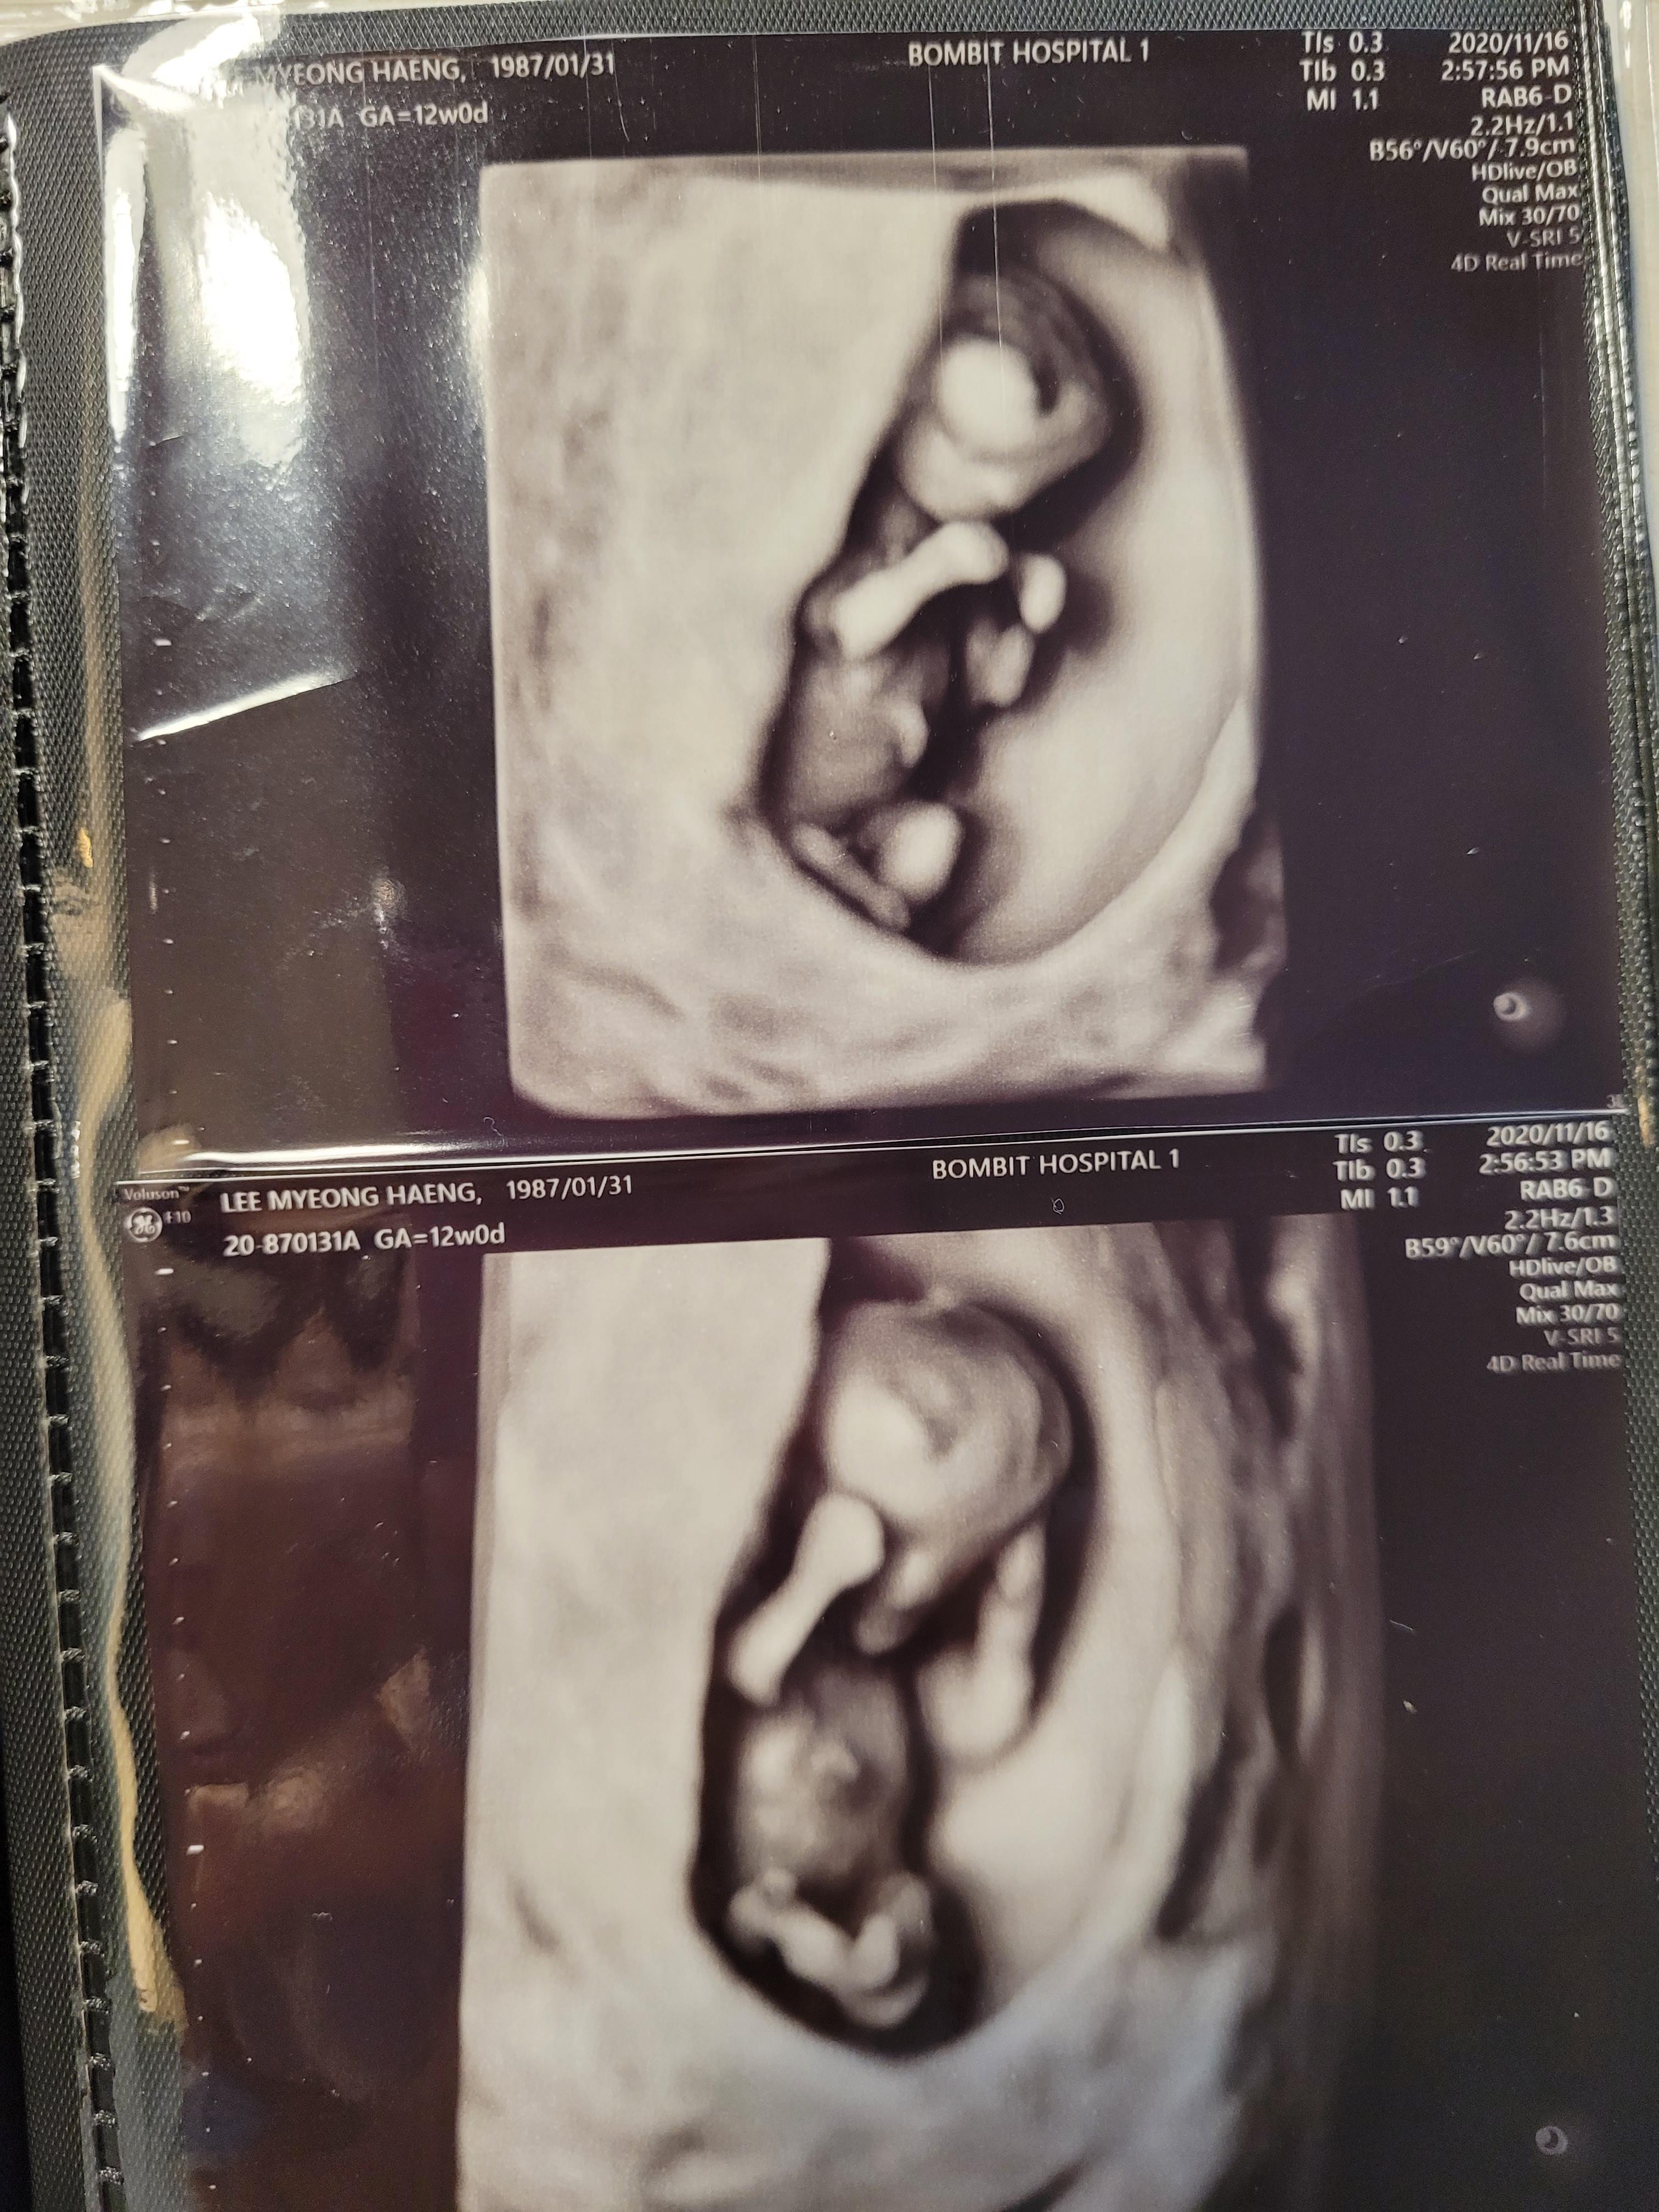

입체초음파를 보고, 다시 진료실에와서 주치의 원장님과 다시 초음파검사를 했어요.

넘넘 귀여운 아가^^

꼬물꼬물 너무 잘움직이고 귀엽더라고요.

입덧때문에 잘 못먹었는데도, 잘 자라주어서 고마웠어요.